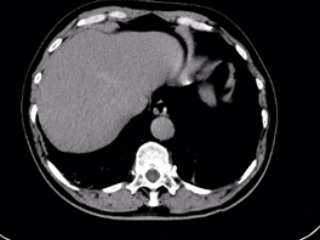

▲术后